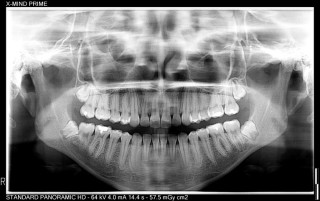

Tomograf X-Mind Prime 2 Pano 3D cechuje wielkość woksela na poziomie 72,5 μm oraz dostępność szerokiego zakresu FOV od 50 x 50 do 120 x 100 mm. W połączeniu z automatycznym doborem ustawień i dawki zyskujesz pewność dokładnego zbadania najmniejszych elementów anatomicznych w 3D. Wszystko to przy zaledwie 7-sekundowym czasie ekspozycji, potrzebnym do uzyskania obrazu pełnego uzębienia.

X-Mind Prime 2 Pano 3D pozwala na przeprowadzenie badań 2D i 3D, w tym uzyskanie kompletnego panoramicznego widoku szczęki i żuchwy, zatok szczękowych, stawów skroniowo-żuchwowych, a także wszystkich struktur wokół nich. Za pomocą urządzenia wykonasz m.in: